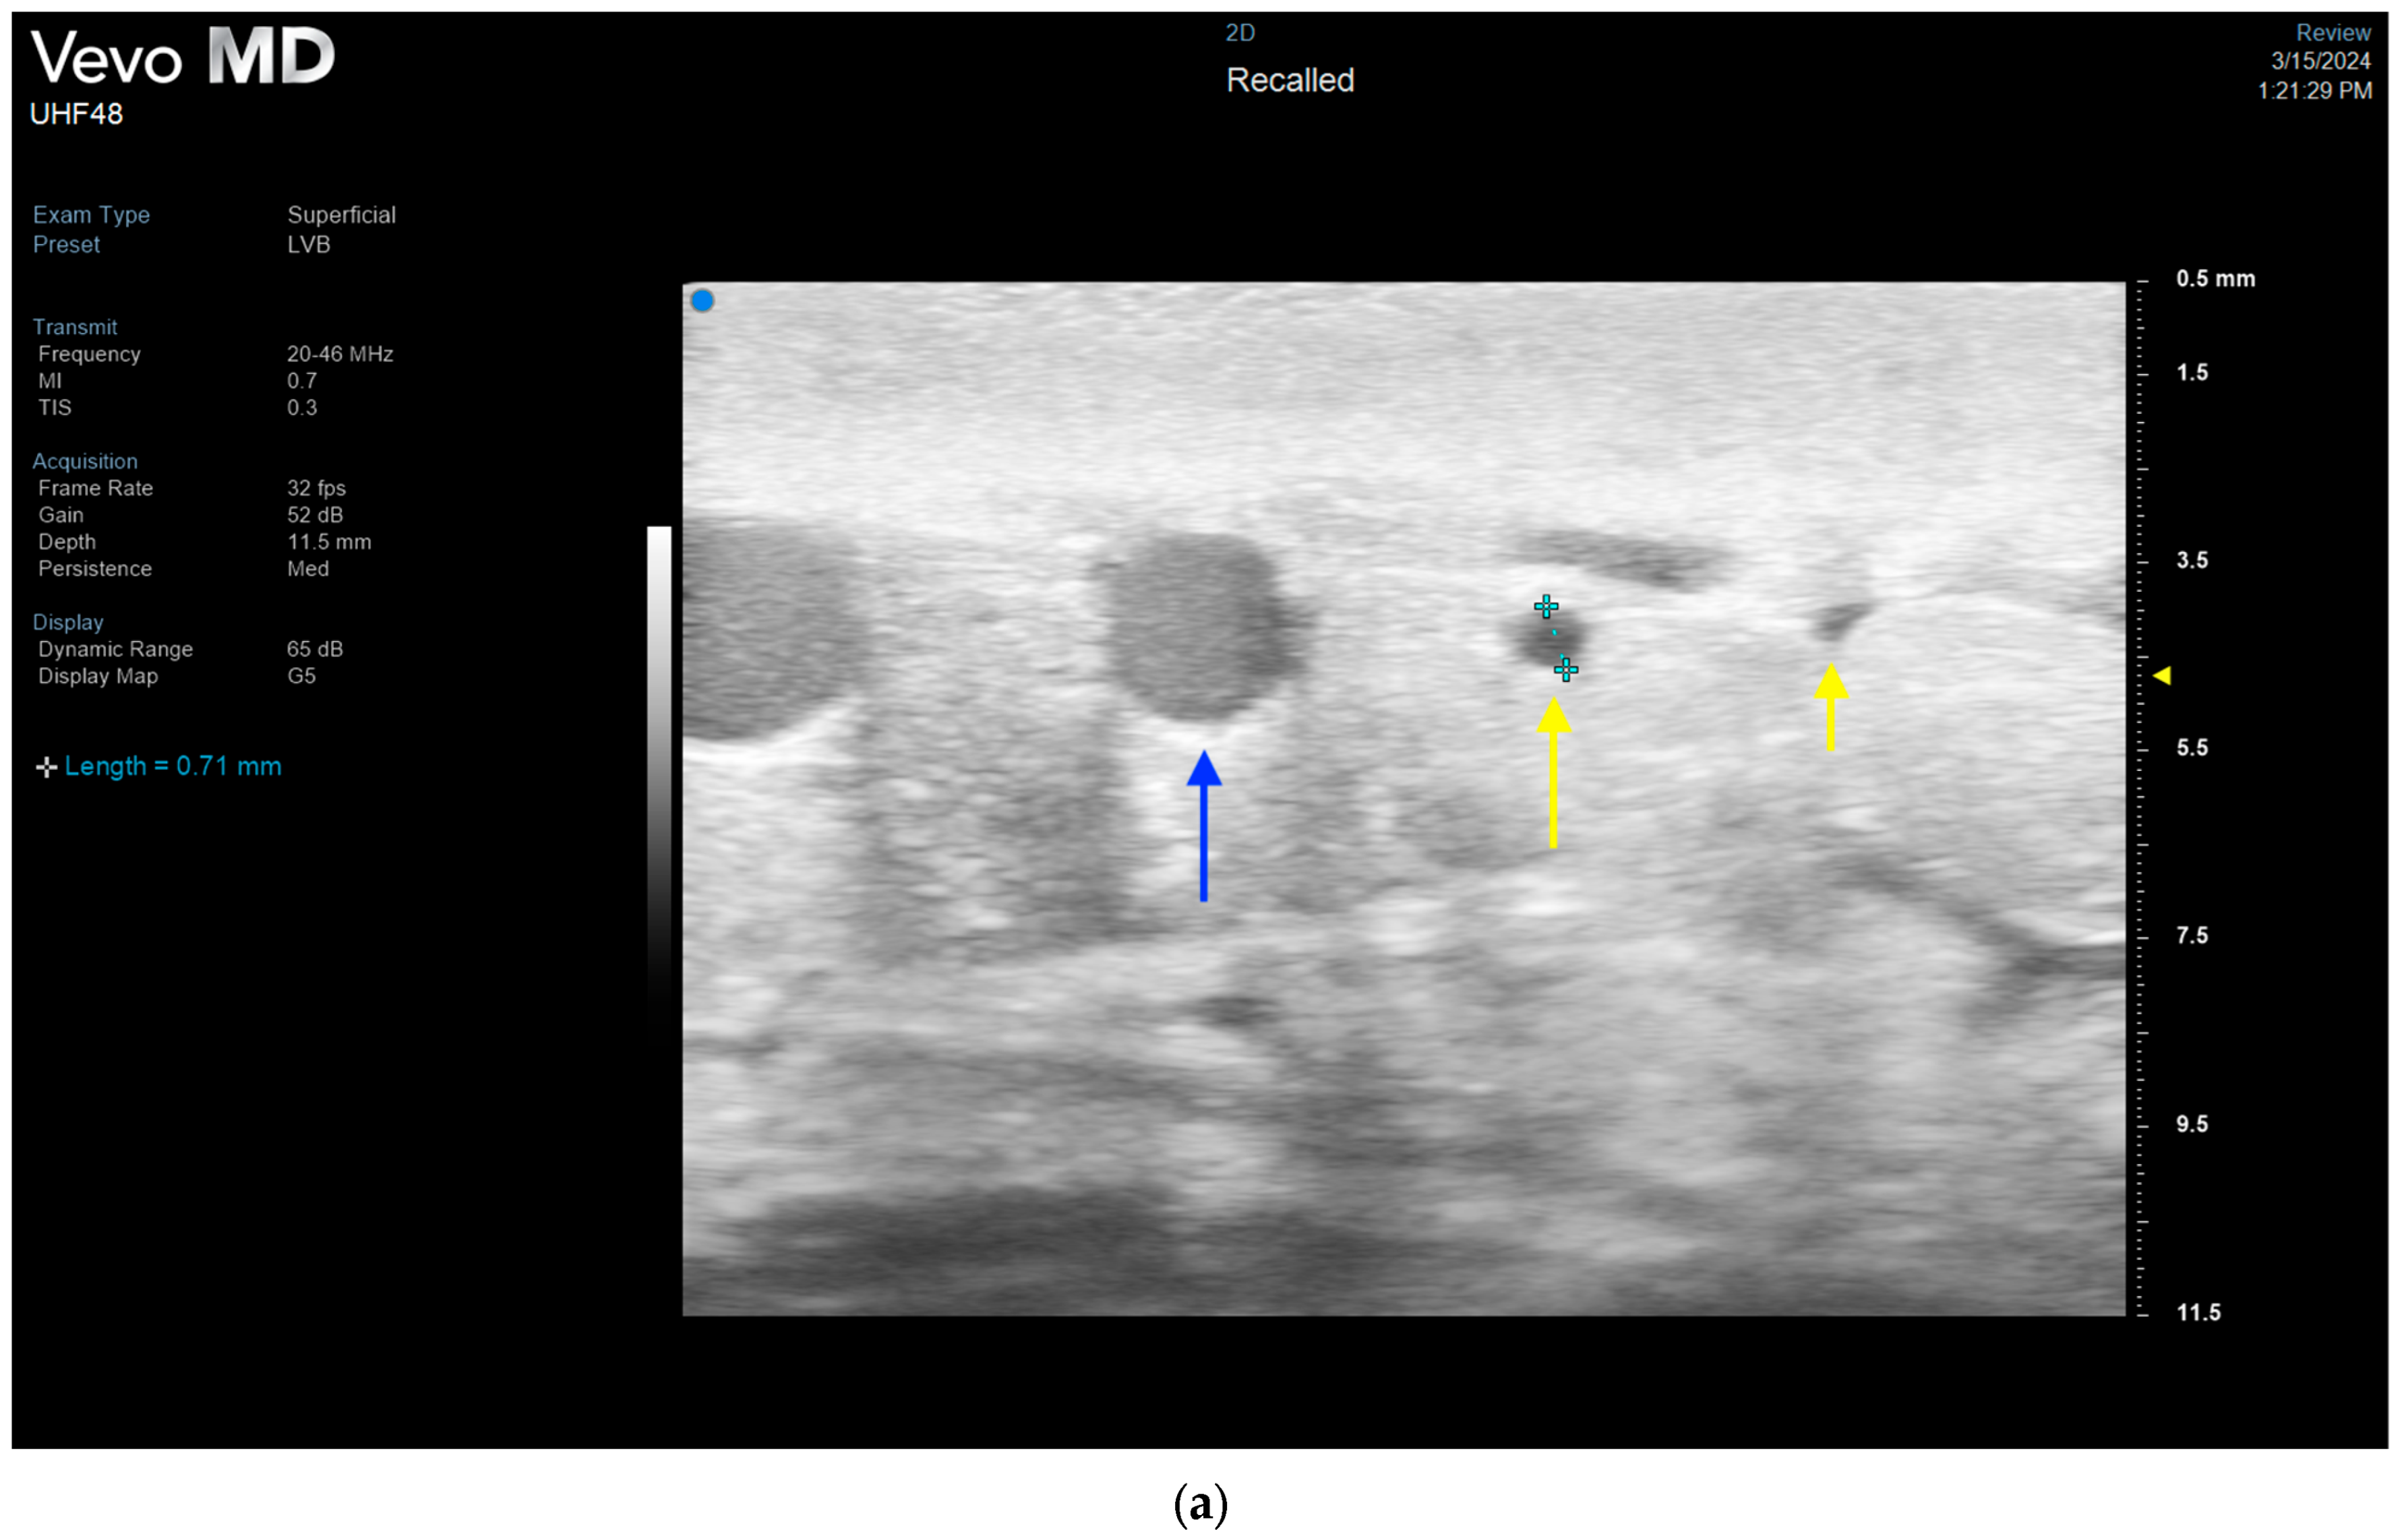

3.4. Lymphatic Surgery

- Hayashi, A.; Giacalone, G.; Yamamoto, T.; Belva, F.; Visconti, G.; Hayashi, N.; Handa, M.; Yoshimatsu, H.; Salgarello, M. Ultra High-frequency Ultrasonographic Imaging with 70 MHz Scanner for Visualization of the Lymphatic Vessels. Plast. Reconstr. Surg.-Glob. Open 2019, 7, e2086. [Google Scholar] [CrossRef] [PubMed]

- Hayashi, A.; Visconti, G.; Giacalone, G.; Hayashi, N.; Yoshimatsu, H. Recent Advances in Ultrasound Technology: Ultra-High Frequency Ultrasound for Reconstructive Supermicrosurgery. J. Reconstr. Microsurg. 2022, 38, 193–199. [Google Scholar] [CrossRef] [PubMed]

- Bianchi, A.; Visconti, G.; Hayashi, A.; Santoro, A.; Longo, V.; Salgarello, M. Ultra-High frequency ultrasound imaging of lymphatic channels correlates with their histological features: A step forward in lymphatic surgery. J. Plast. Reconstr. Aesthetic Surg. 2020, 73, 1622–1629. [Google Scholar] [CrossRef] [PubMed]

- Czedik-Eysenberg, M.; Steinbacher, J.; Obermayer, B.; Yoshimatsu, H.; Hara, H.; Mihara, M.; Tzou, C.J.; Meng, S. Exclusive use of ultrasound for locating optimal LVA sites—A descriptive data analysis. J. Surg. Oncol. 2019, 121, 51–56. [Google Scholar] [CrossRef] [PubMed]

- Seki, Y.; Kajikawa, A.; Yamamoto, T.; Takeuchi, T.; Terashima, T.; Kurogi, N. The dynamic-lymphaticovenular anastomosis method for breast cancer treatment-related lymphedema: Creation of functional lymphaticovenular anastomoses with use of preoperative dynamic ultrasonography. J. Plast. Reconstr. Aesthetic Surg. 2019, 72, 62–70. [Google Scholar] [CrossRef] [PubMed]